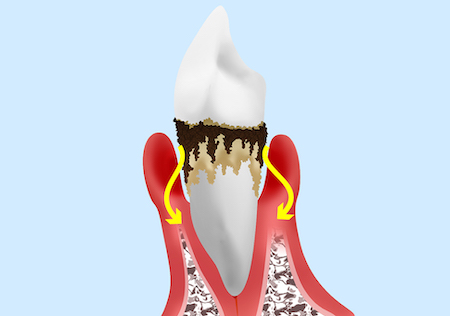

歯周病というのは歯が植わっている土台のアゴの骨を溶かす病気です。

このように歯周病は土台のアゴの骨を溶かしていきます。アゴの骨が溶け続けることにより最終的には歯がグラグラになり抜け落ちていく病気です。

歯周病菌は、唾液や口の中に入る食事を栄養源として増殖し常時毒素を出します→その毒素によって歯を支えている骨を溶かしていきます。

ここで見ていただきたいのは、健康な方と重度歯周病の方の歯茎の高さはあまり変わらないという所です。要するにパッとお口の中だけを見て歯周病かどうかは分かりません。

X線写真の検査をしてはじめてどれだけ骨が溶けて歯周病が進行したかがわかります。